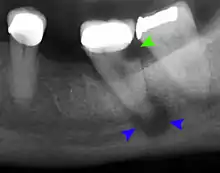

- Radiographs utilized to find dental caries and bone loss laterally or at the apex.

Decay (green) with apical abscess (blue)

Gutta-percha point indicating abscess origin